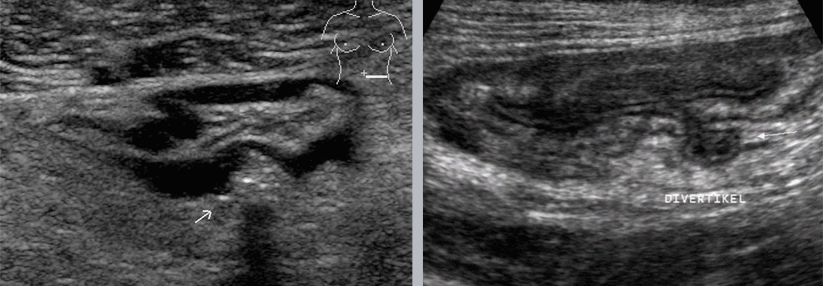

Die Diagnostik erfolgt mittels einer klinischen Untersuchung, Sonografie sowie Computertomografie des Abdomens. Manchmal wird auch auf eine Koloskopie zurückgegriffen, die jedoch gerade in einer akuten Phase ein erhöhtes Perforationsrisiko birgt.

Als Divertikulitis wird eine Erkrankung des Dickdarmes bezeichnet, bei der sich die Divertikel (Ausstülpungen der Darmwand) entzünden. Die Divertikulose des Kolons, eine Vorstufe der Divertikulitis, ist eine der häufigsten gutartigen Veränderungen des Gastrointestinaltrakts. Allerdings handelt es sich um Pseudodivertikel, also Ausstülpungen der Mukosa und Submukosa an Eintrittsstellen der Arteriolen. Während die Divertikulose bei unter 40-Jährigen selten ist, steigt die Prävalenz mit zunehmendem Lebensalter auf ca. 65 % bei 85-jährigen an. Menschen, deren Darm Divertikel ausgebildet hat, erkranken zu etwa 12 - 25 % an einer Divertikulitis.